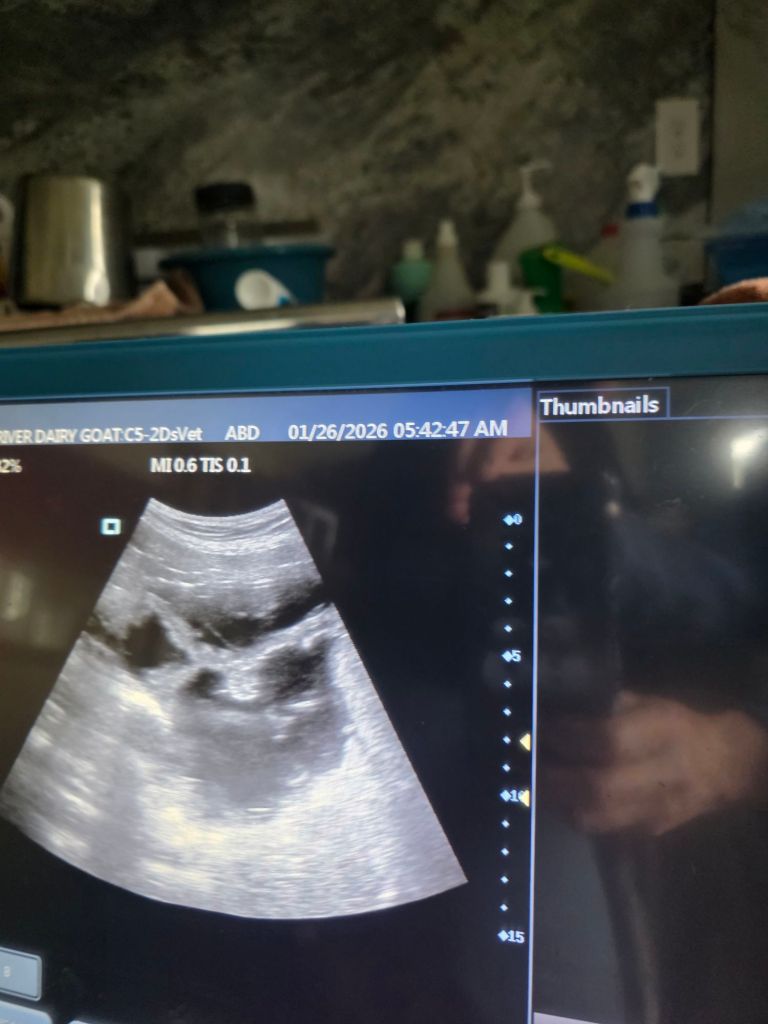

January 26, 2026

Ultrasounds are completed